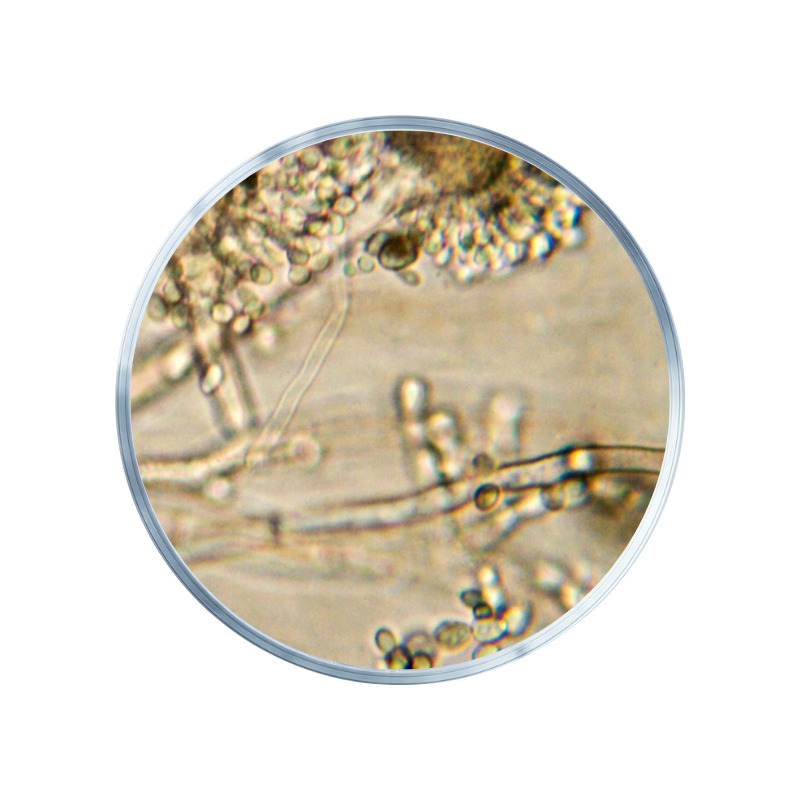

Lipocarnine™ blend is de eerste Europese blend met bio-actieve eiwitstructuren; om het metabolisme te ondersteunen. Dit met aandacht voor vetoxidatie² en behoud van spiermassa¹.

Lipocarnine™ is een krachtige blend met actieve ingrediënten zoals bio-actieve eiwitpeptides die GIP stimuleren, een belangrijk verzadigingshormoon. Het stimuleert eveneens het transport van vetzuren in het lichaam.

Bioactieve peptiden ontstaan wanneer eiwitten in kleinere stukjes worden afgebroken. Deze kleine moleculen kunnen invloed uitoefenen op processen zoals eetlust, verzadiging en vetverwerking. Sommige stimuleren de aanmaak van hormonen die ervoor zorgen dat je je langer vol voelt (zie hierna).

GIP staat voor Gastric Inhibitory Polypeptide. Dit verzadigingshormoon komt vrij na de maaltijd, vooral als er vetten of suikers zijn gegeten. GIP heeft eveneens een vertragende invloed op de maaglediging. Tot slot is het hormoon ook betrokken bij vetopslag in het lichaam.